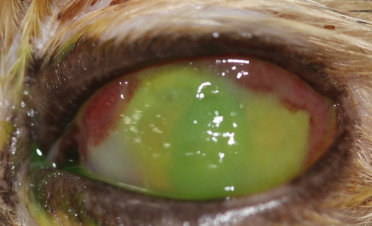

Durante la exploración oftalmológica, tras instilar una gota de colirio anestésico, pudimos observar una úlcera corneal infectada (úlcera colagenasa o “melting”).

La úlcera abarcaba prácticamente el 90% de la córnea, presentaba una gran inflamación en la conjuntiva y vasos sanguíneos en la periferia de la misma.

Las úlceras colagenasa o “melting” son úlceras altamente infectadas que afectan a capas medias y profundas de la córnea, pudiendo incluso llegar a perforar el ojo. Debido a las enzimas proteolíticas y colagenasas que liberan las bacterias, la córnea pierde su rigidez y adopta una tonalidad azulada y un aspecto gelatinoso, de ahí su apodo “úlcera melting”.